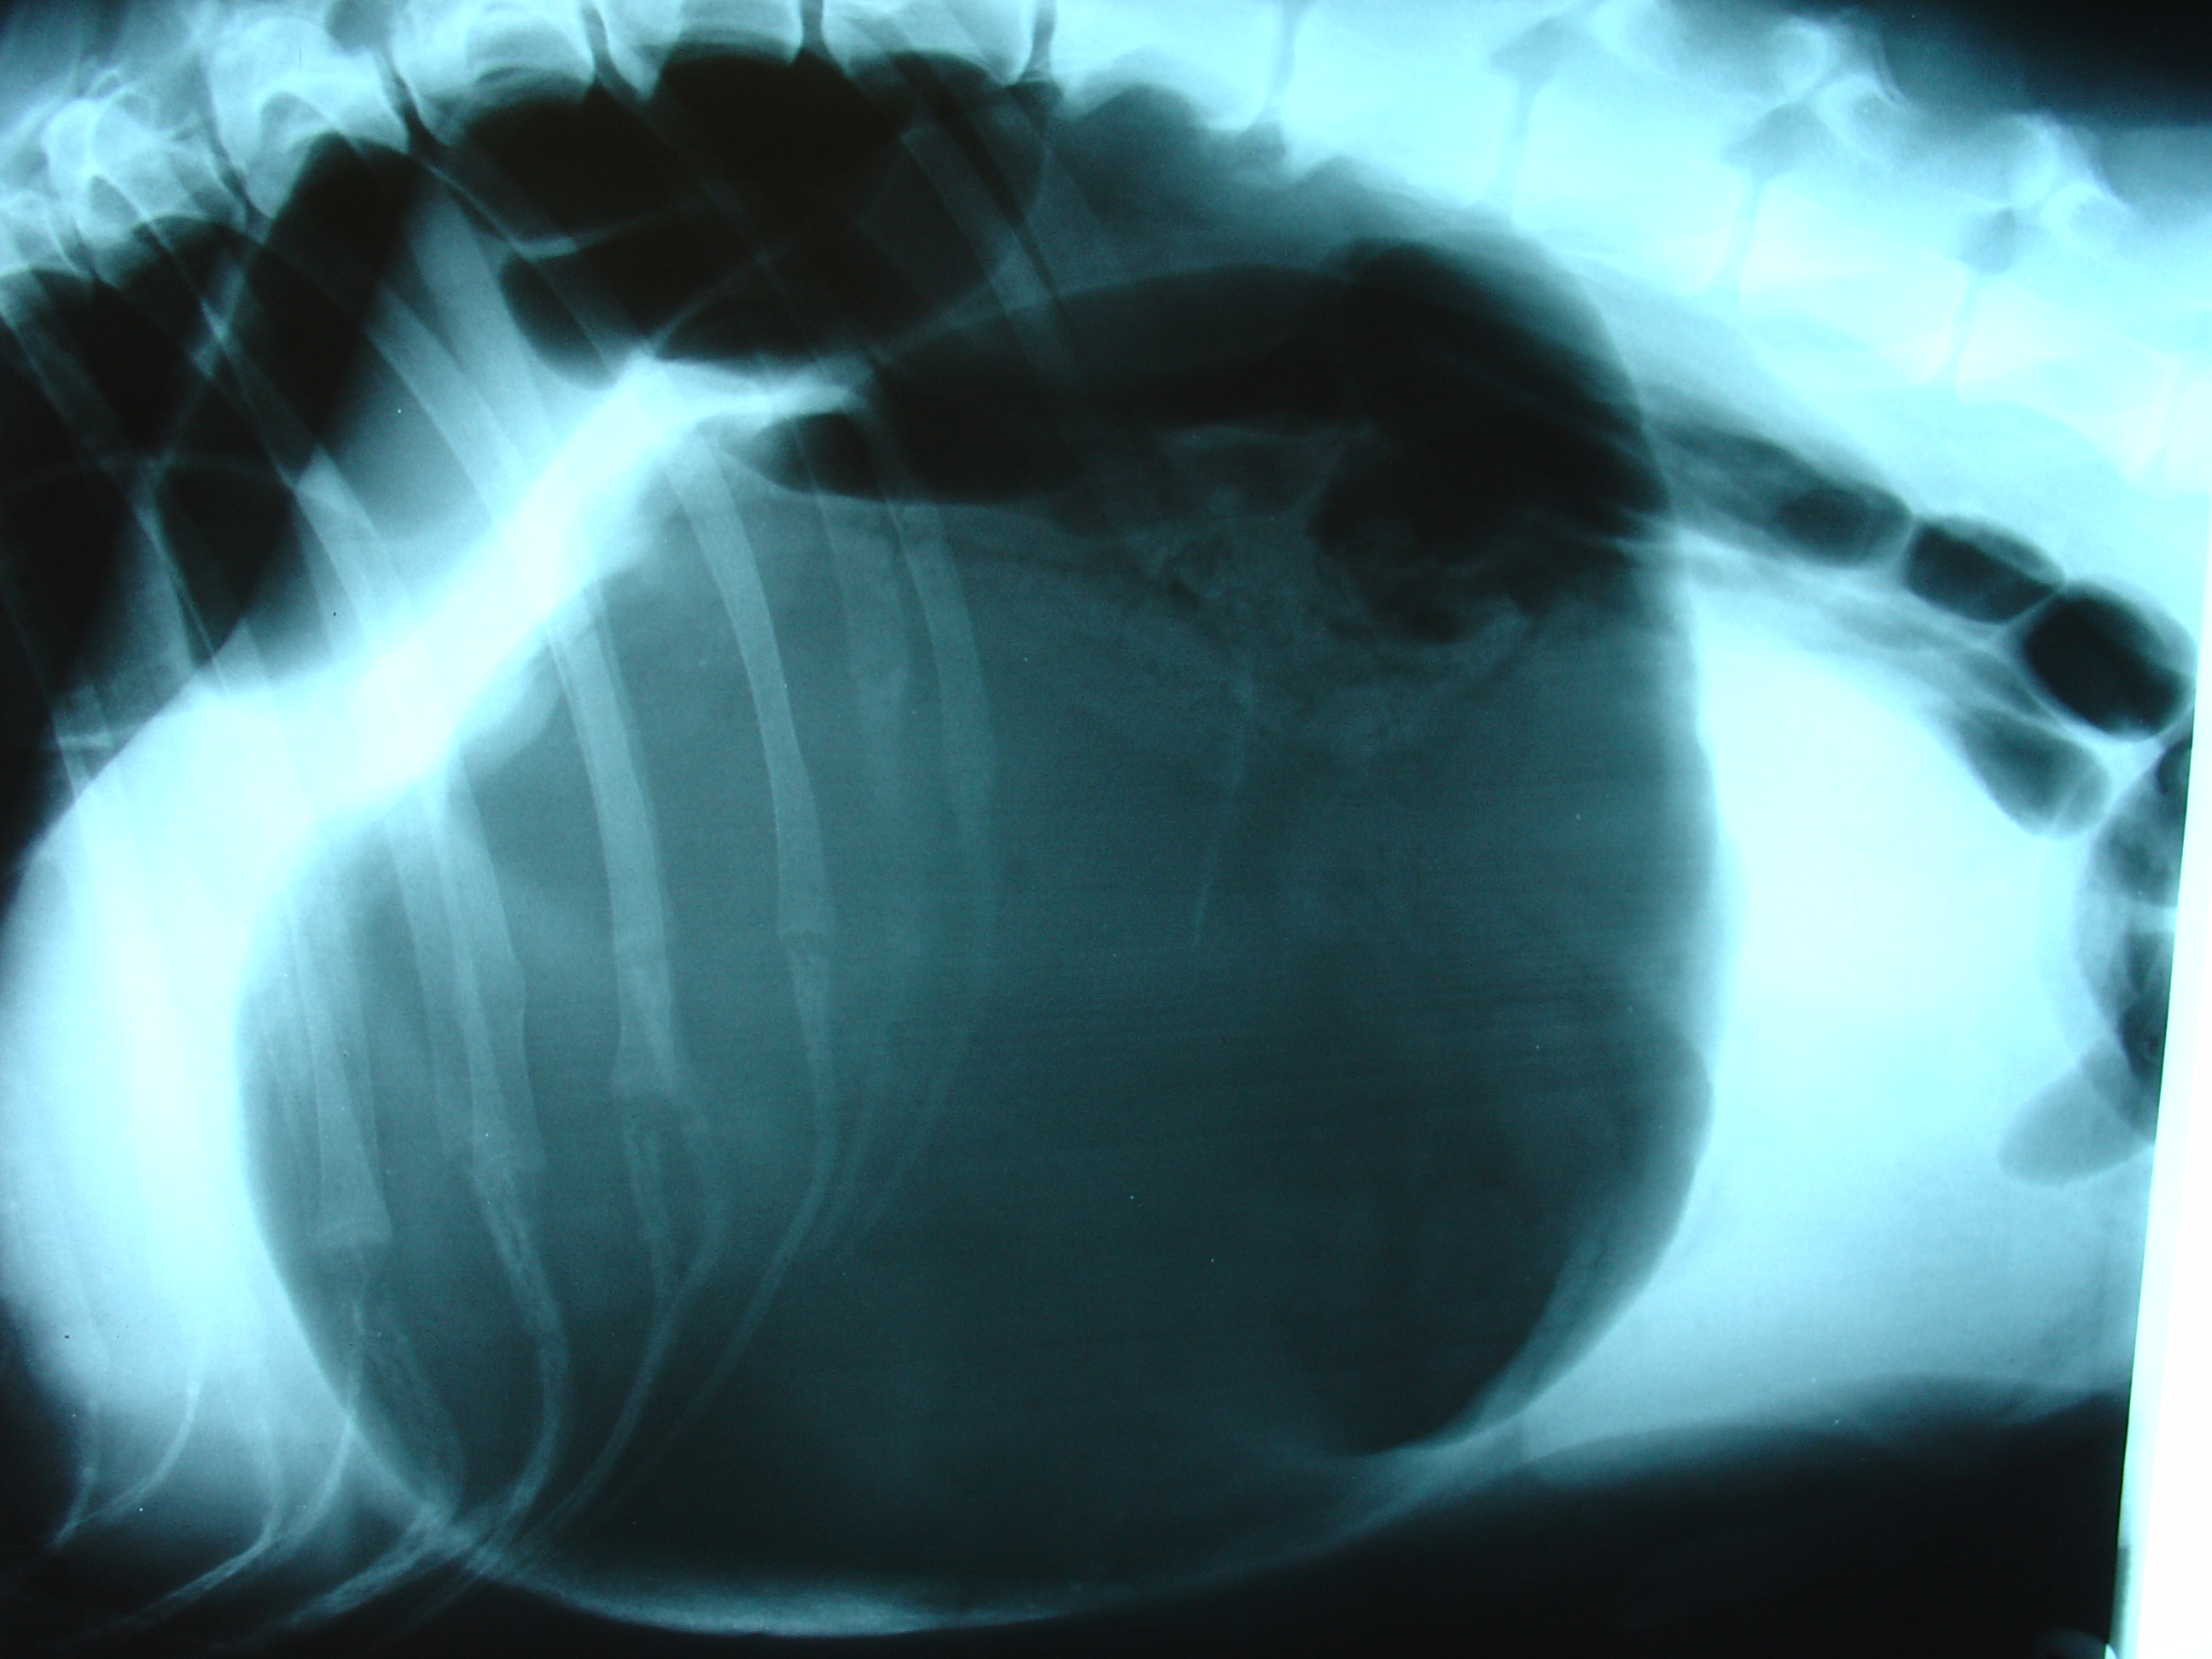

Les signes cliniques de torsion gastrique sont facilement identifiables – le chien fait des efforts de vomissements, mais ces efforts sont improductifs – rien ne sort. L’animal présente une salivation importante, une distension abdominale et des signes de douleur. Puis, on note un abattement qui s’aggrave rapidement. Dès que les premiers signes sont observés, il est impératif de se rendre d’urgence chez un vétérinaire. Le diagnostic est facilement confirmé par l’examen physique et la prise de radiographies abdominales.